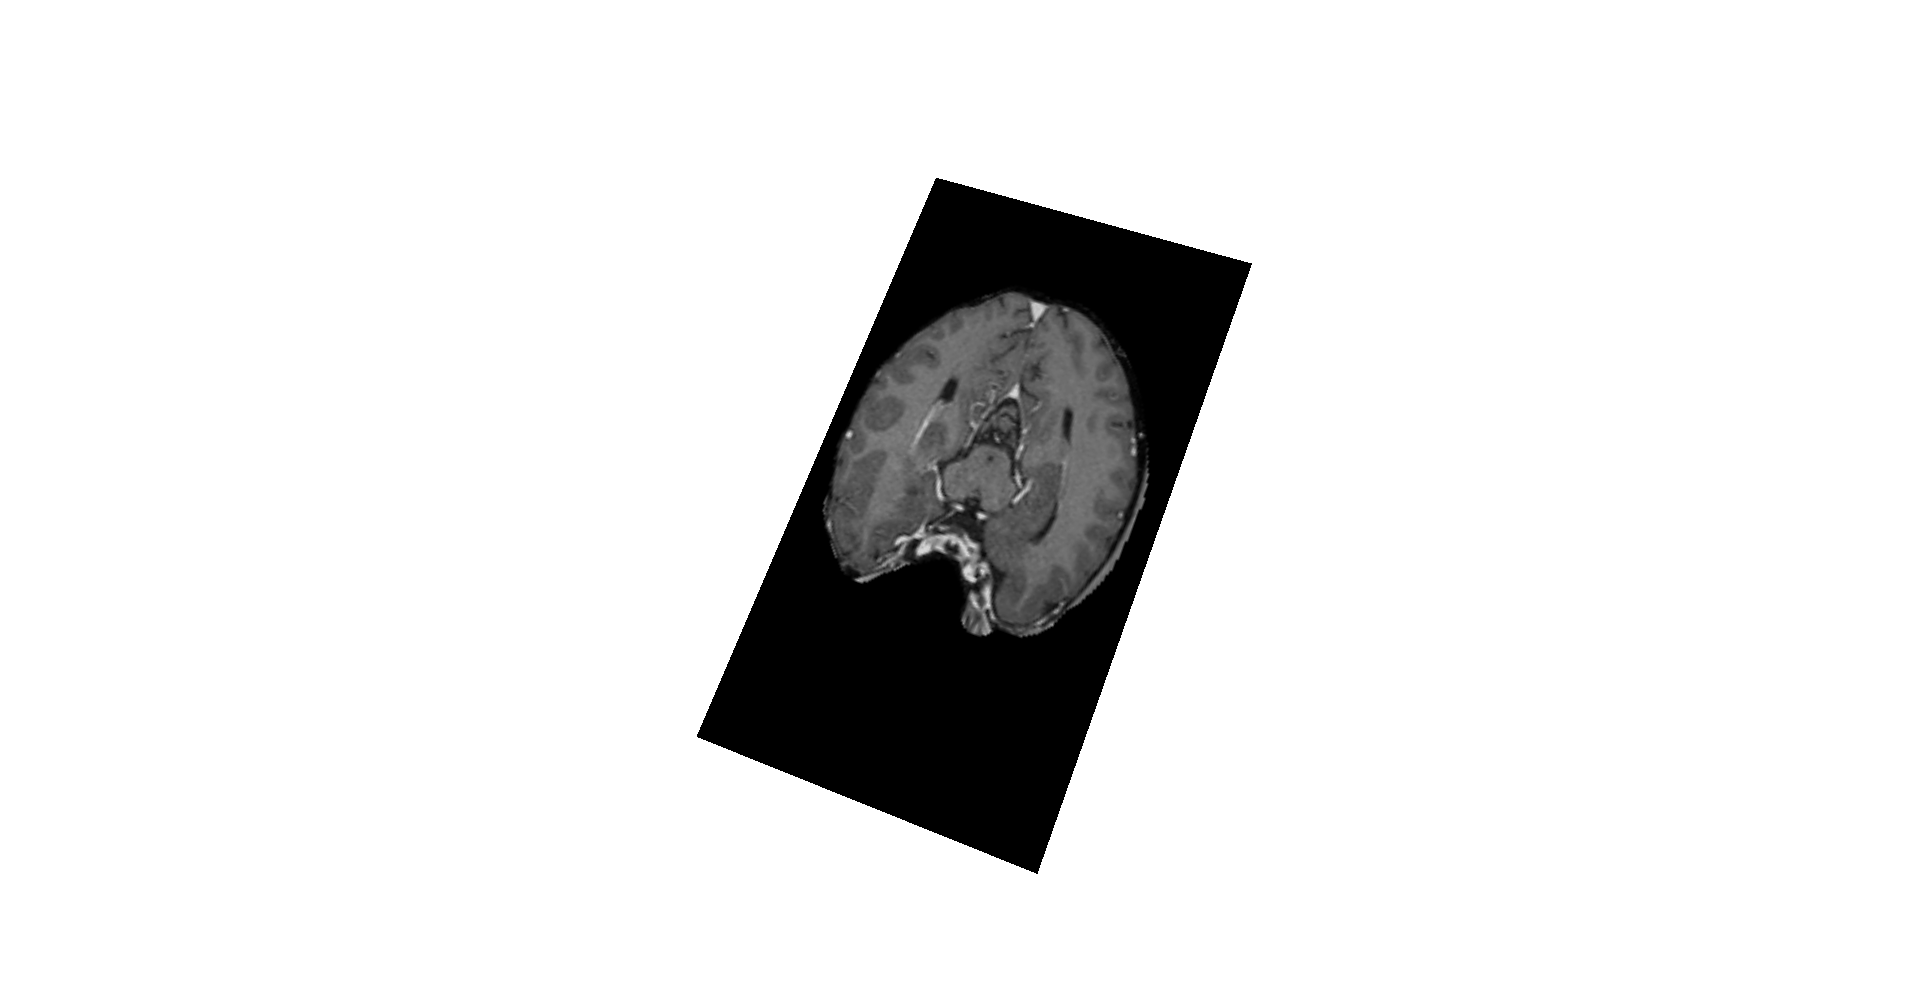

VolumeViz Demonstration of ColorWash using Intensity and Anisotropy.

A shader is used to merge the two data sets. The Diffusion Tensor Imaging Diffusion Weighted Imaging (DWI) and the Diffusion Tensor Imaging (DTI) are relatively new imaging techniques which are designed to identify and visualize structures such as fiber tracts, tumors, or stroke areas in living tissues that are invisible to other image techniques.

Combined:

IntensityAnisotropy_sliceFrag.glsl is in charge of this combination.

SCREENSHOT: